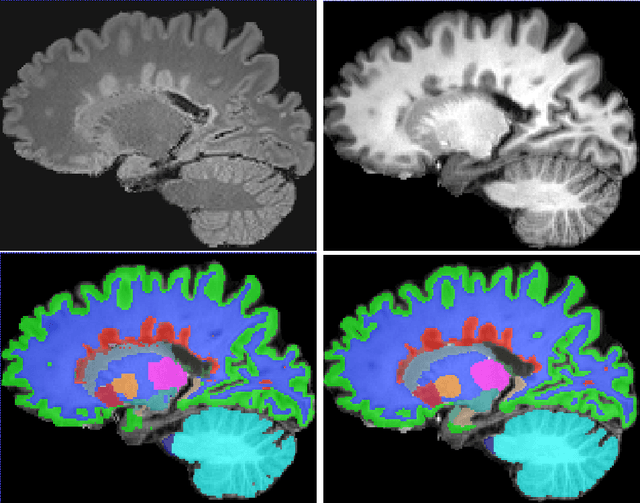

Abstract:Segmentation of both white matter lesions and deep grey matter structures is an important task in the quantification of magnetic resonance imaging in multiple sclerosis. Typically these tasks are performed separately: in this paper we present a single CNN-based segmentation solution for providing fast, reliable segmentations of multimodal MR imagies into lesion classes and healthy-appearing grey- and white-matter structures. We show substantial, statistically significant improvements in both Dice coefficient and in lesion-wise specificity and sensitivity, compared to previous approaches, and agreement with individual human raters in the range of human inter-rater variability. The method is trained on data gathered from a single centre: nonetheless, it performs well on data from centres, scanners and field-strengths not represented in the training dataset. A retrospective study found that the classifier successfully identified lesions missed by the human raters. Lesion labels were provided by human raters, while weak labels for other brain structures (including CSF, cortical grey matter, cortical white matter, cerebellum, amygdala, hippocampus, subcortical GM structures and choroid plexus) were provided by Freesurfer 5.3. The segmentations of these structures compared well, not only with Freesurfer 5.3, but also with FSL-First and Freesurfer 6.1.